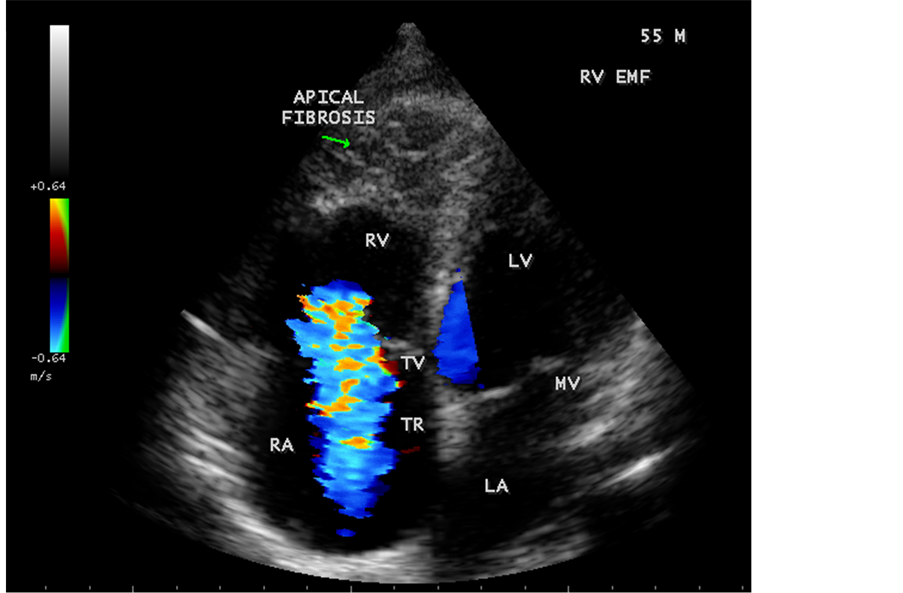

pressure 100/70 mmHg. Auscultation revealed diminished breath sounds on the right side of the chest with a dull note on percussion and a loud P2 (pulmonic component of second heart sound) with grade 2/6 soft systolic murmur over the lower left sternal border which increases in intensity with deep inspiration (Carvallo’s sign) suggesting tricuspid regurgitation. ECG revealed no arrhythmias and X-ray chest showed right- sided pleural effusion and extensive calcification over the cardiac shadow as shown in Figure 9. Transthoracic echocardiography revealed apical fibrosis of right ventricle, moderate pericardial effusion, right atrial dilatation as shown in Figure 10 and Figure 12, suggesting right ventricular endomyocardial fibrosis and severe tricuspid regurgitation as in Figure 11, Figure 13 and Figure 14 indicates coexisting pulmonary hypertension due to pulmonary damage caused by tuberculosis as shown in Figure 13 and free RV outflow tract as in Figure 15. Patient was treated with antituberculous drugs, antifailure measures such as digoxin and diuretics, ascites fluid tapping and antibiotics. He showed mild improvement in his symptoms.

Figure 11. Apical four chamber view suggesting RV (right ventricular) apical fibrosis, RA dilatation and severe tricuspid regurgitation suggesting right ventricular endomyocardial fibrosis with an extension of fibrosis in the LV apex.

Figure 12. Apical four chamber view showing the RV apical fibrosis with mild pericardial effusion in a 23-year-old male with tuberculosis.

Figure 83. Classical RV EMF with apical fibrosis in a 55-year-old male.

Figure 84. Classical RV EMF with apical fibrosis and tricuspid regurgitation in a 55-year-old male.